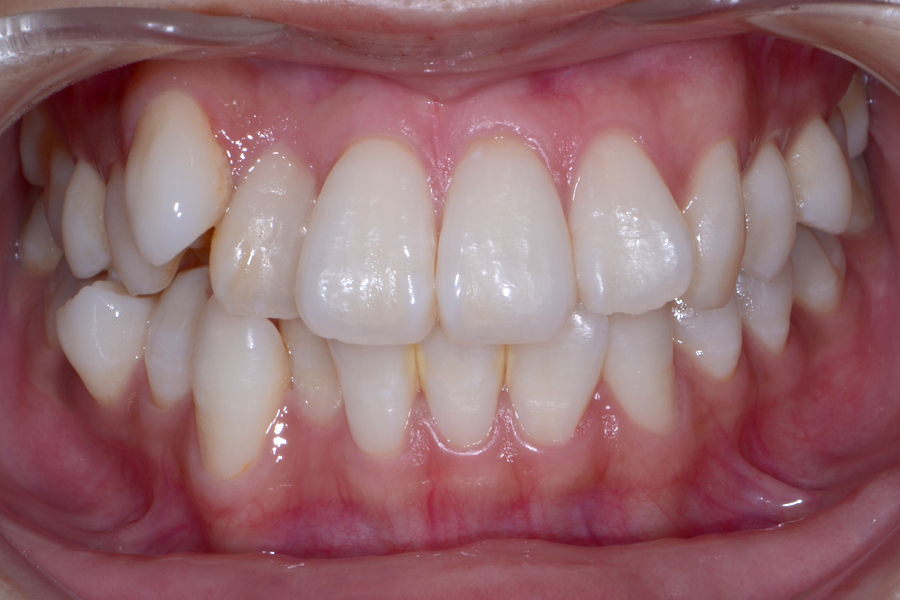

• 治療前

治療後

主訴 下の一本飛び出ている歯だけ治したい

治療内容 下顎ラビアル矯正(表側矯正)

リスク 後戻り